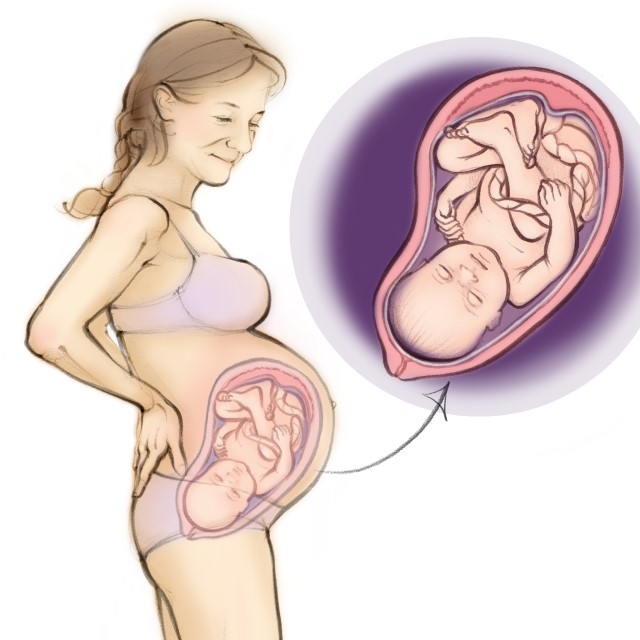

Your developing baby

You are now in week 38 of your pregnancy, and the wait to meet your baby is nearing the end. They are putting on weight in order to be able to control their body temperature outside the womb and to protect their organs.

They’re also building up waste made out of amniotic fluid, blood and skin in their intestines which they will excrete after they’re born. This, is called meconium.